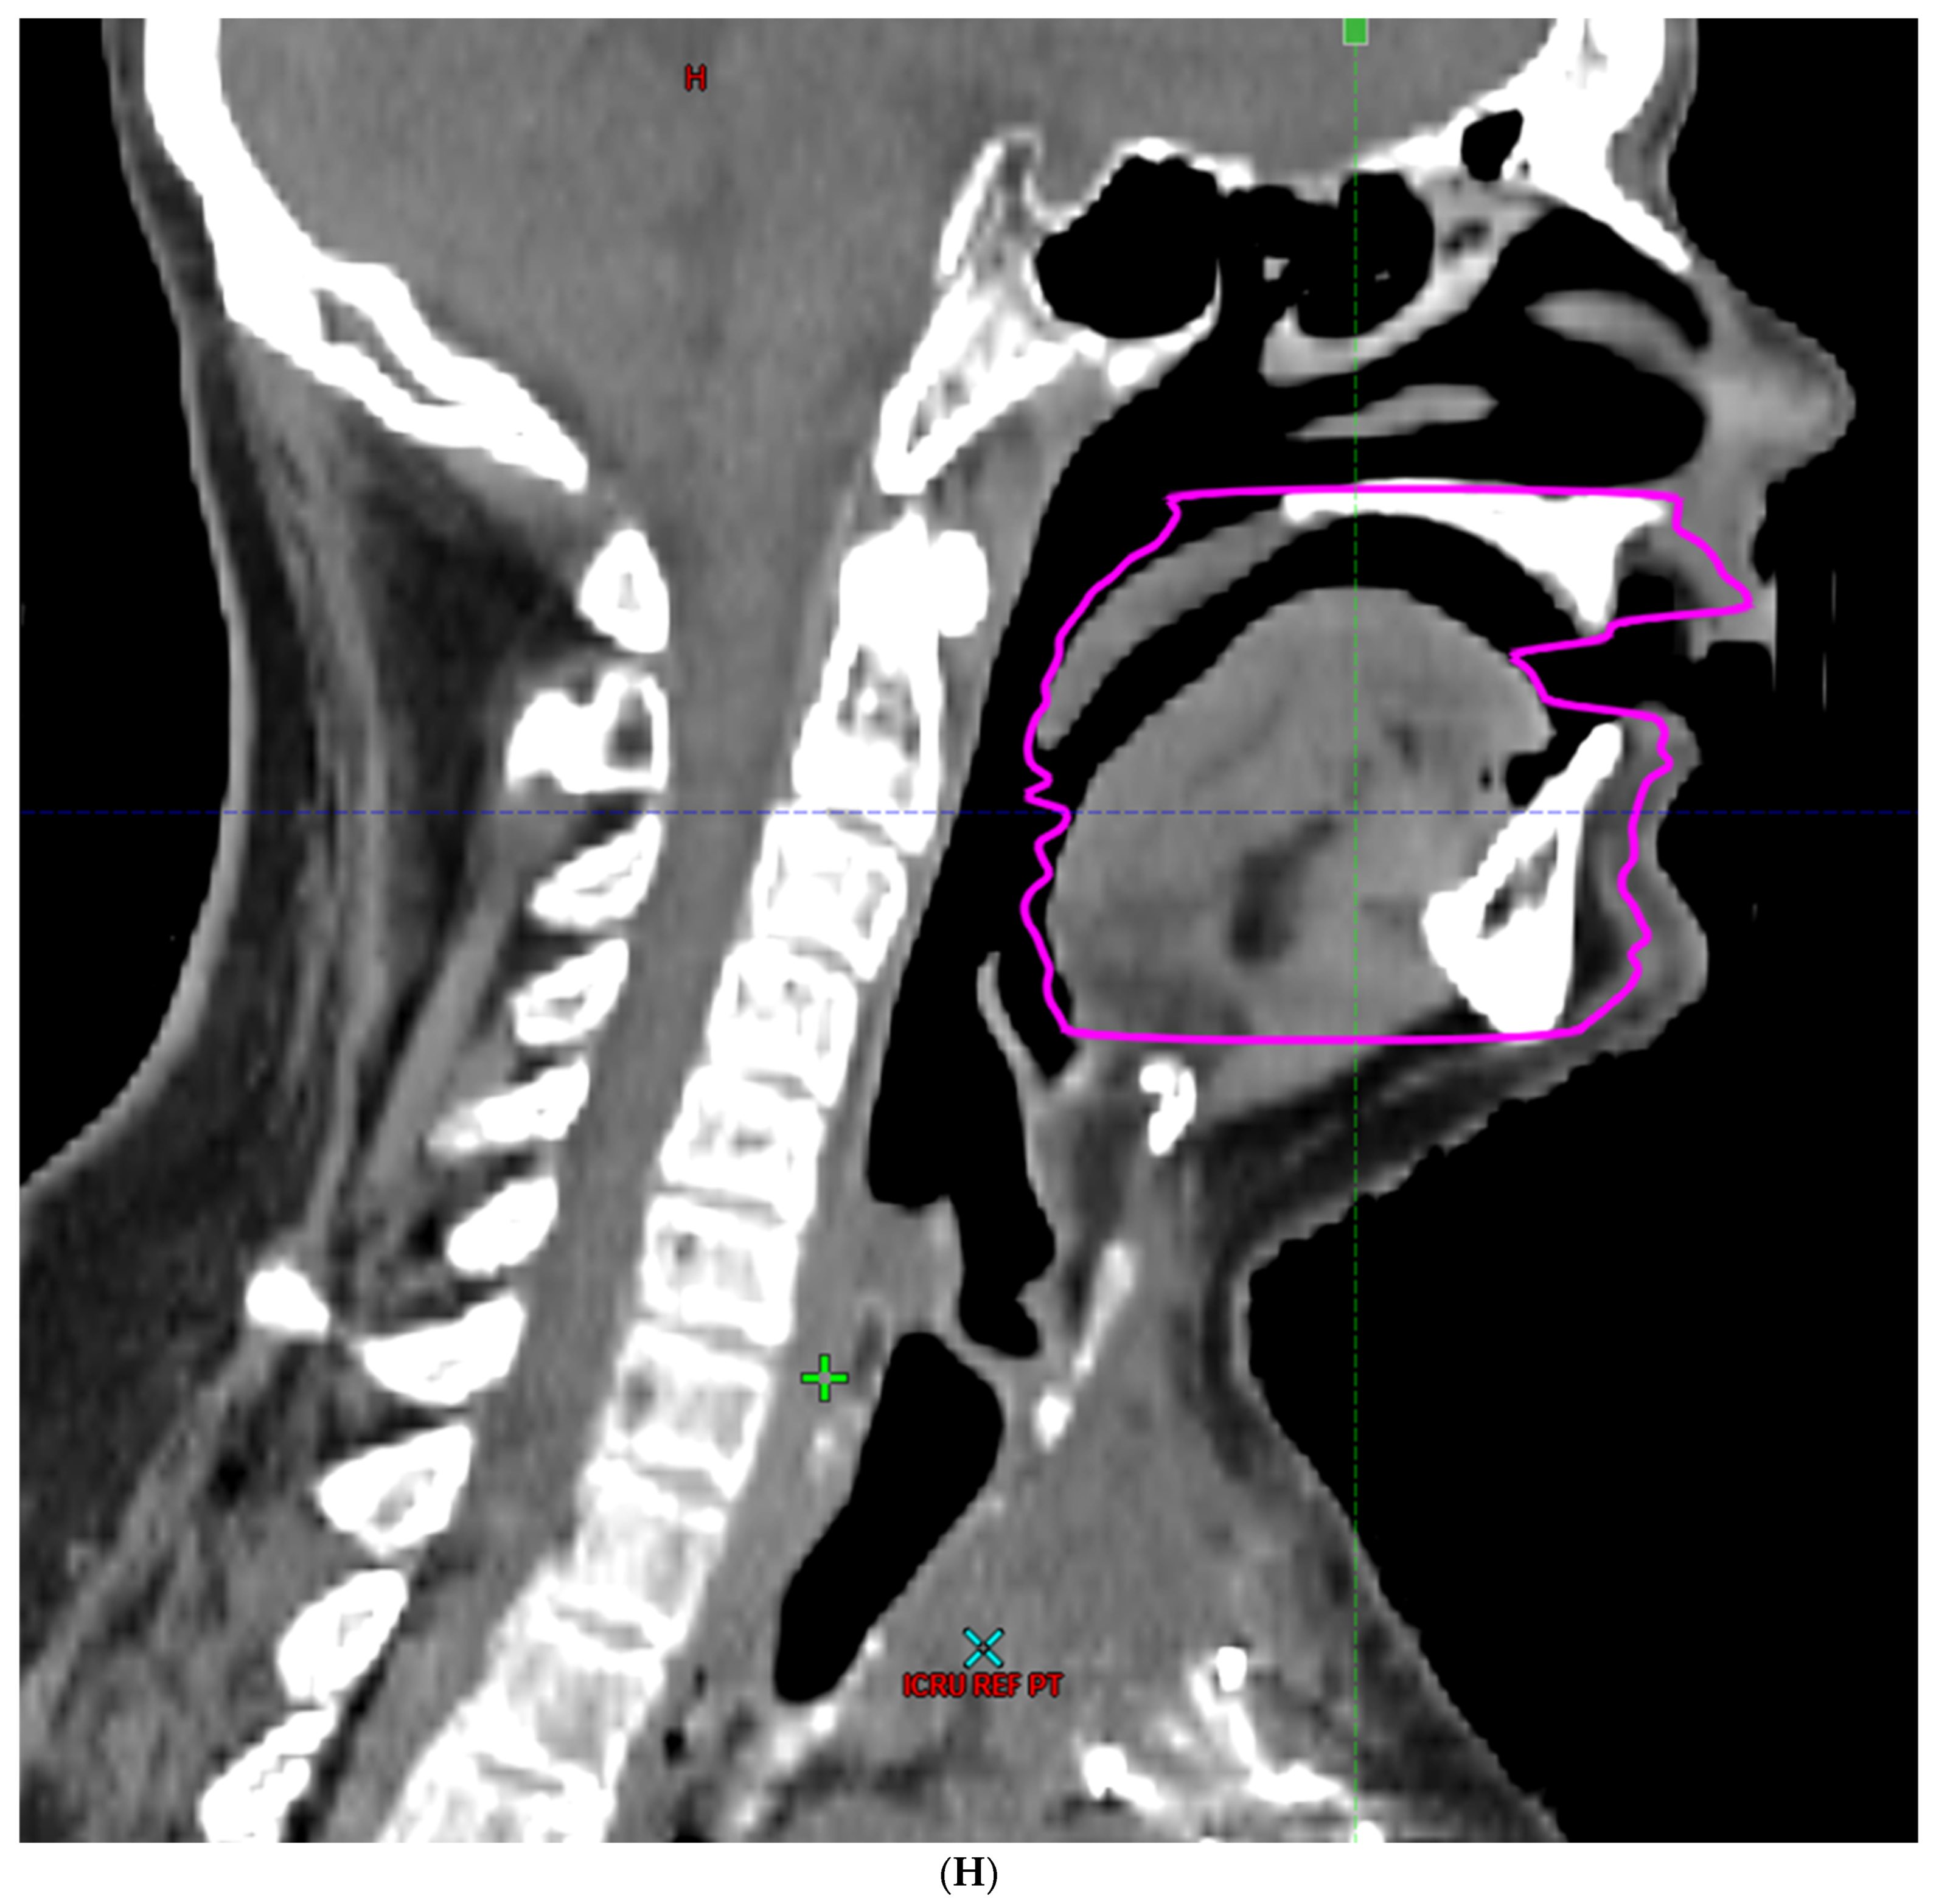

- Hoebers, F.; Yu, E.; Thorstad, W.; O’Sullivan, B.; Dawson, L.A.; Hope, A. A Pragmatic Contouring Guideline for Salivary Gland Structures in Head and Neck Radiation Oncology. The MOIST Target. Am. J. Clin. Oncol. 2013, 36, 70–76. [Google Scholar] [CrossRef]

- Brouwer, C.L.; Steenbakkers, R.J.; Bourhis, J.; Budach, W.; Grau, C.; Grégoire, V.; Van Herk, M.; Lee, A.; Maingon, P.; Nutting, C.; et al. CT-based delineation of organs at risk in the head and neck region: DAHANCA, EORTC, GORTEC, HKNPCSG, NCIC CTG, NCRI, NRG Oncology and TROG consensus guidelines. Radiother. Oncol. 2015, 117, 83–90. [Google Scholar] [CrossRef]

- Li, K.; Yang, L.; Hu, Q.-Y.; Chen, X.-Z.; Chen, M.; Chen, Y. Oral Mucosa Dose Parameters Predicting Grade ≥ 3 Acute Toxicity in Locally Advanced Nasopharyngeal Carcinoma Patients Treated with Concurrent Intensity-Modulated Radiation Therapy and Chemotherapy: An Independent Validation Study Comparing Oral Cavity versus Mucosal Surface Contouring Techniques. Transl. Oncol. 2017, 10, 752–759. [Google Scholar] [CrossRef]

- Sun, Y.; Yu, X.-L.; Luo, W.; Lee, A.W.; Wee, J.T.S.; Lee, N.; Zhou, G.-Q.; Tang, L.-L.; Tao, C.-J.; Guo, R.; et al. Recommendation for a contouring method and atlas of organs at risk in nasopharyngeal carcinoma patients receiving intensity-modulated radiotherapy. Radiother. Oncol. 2014, 110, 390–397. [Google Scholar] [CrossRef]

- Dean, J.A.; Welsh, L.C.; Gulliford, S.L.; Harrington, K.J.; Nutting, C.M. A novel method for delineation of oral mucosa for radiotherapy dose–response studies. Radiother. Oncol. 2015, 115, 63–66. [Google Scholar] [CrossRef]